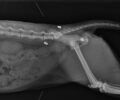

Φωτογραφία: ΑΡΧΕΙΟΥ